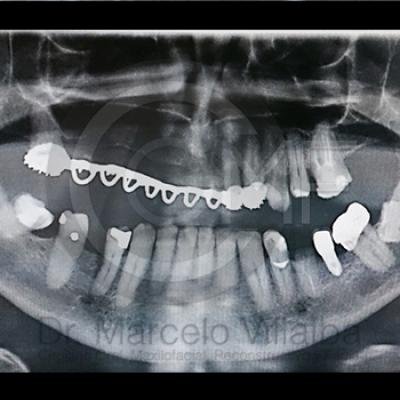

Para el tratamiento de estas patologías se necesita en forma inicial estudios de laboratorio, radiografías o tomografías, estos estudios serán solicitados por el especialista a cada caso en particular, siendo su tratamiento quirúrgico bajo la modalidad de anestesia local o anestesia local más sedación consciente se puede realizar el procedimiento en corto tiempo y buen pronóstico.